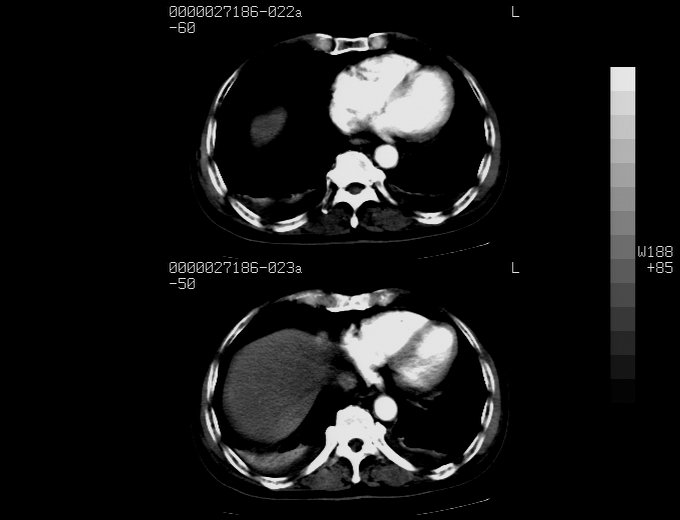

标题: CT16532:M78Y,肝脏病变,请会诊

腹胀,腹痛就诊,男性,78岁,外院b超未见异常。

考虑弥漫性肝癌并脾及双肾转移.双侧胸水.

图片质量欠佳:多考虑:左侧肾癌。脾脏转移!胸膜转移!

肝脾肾转移瘤可能性大,左肾不除外梗塞,双侧胸水